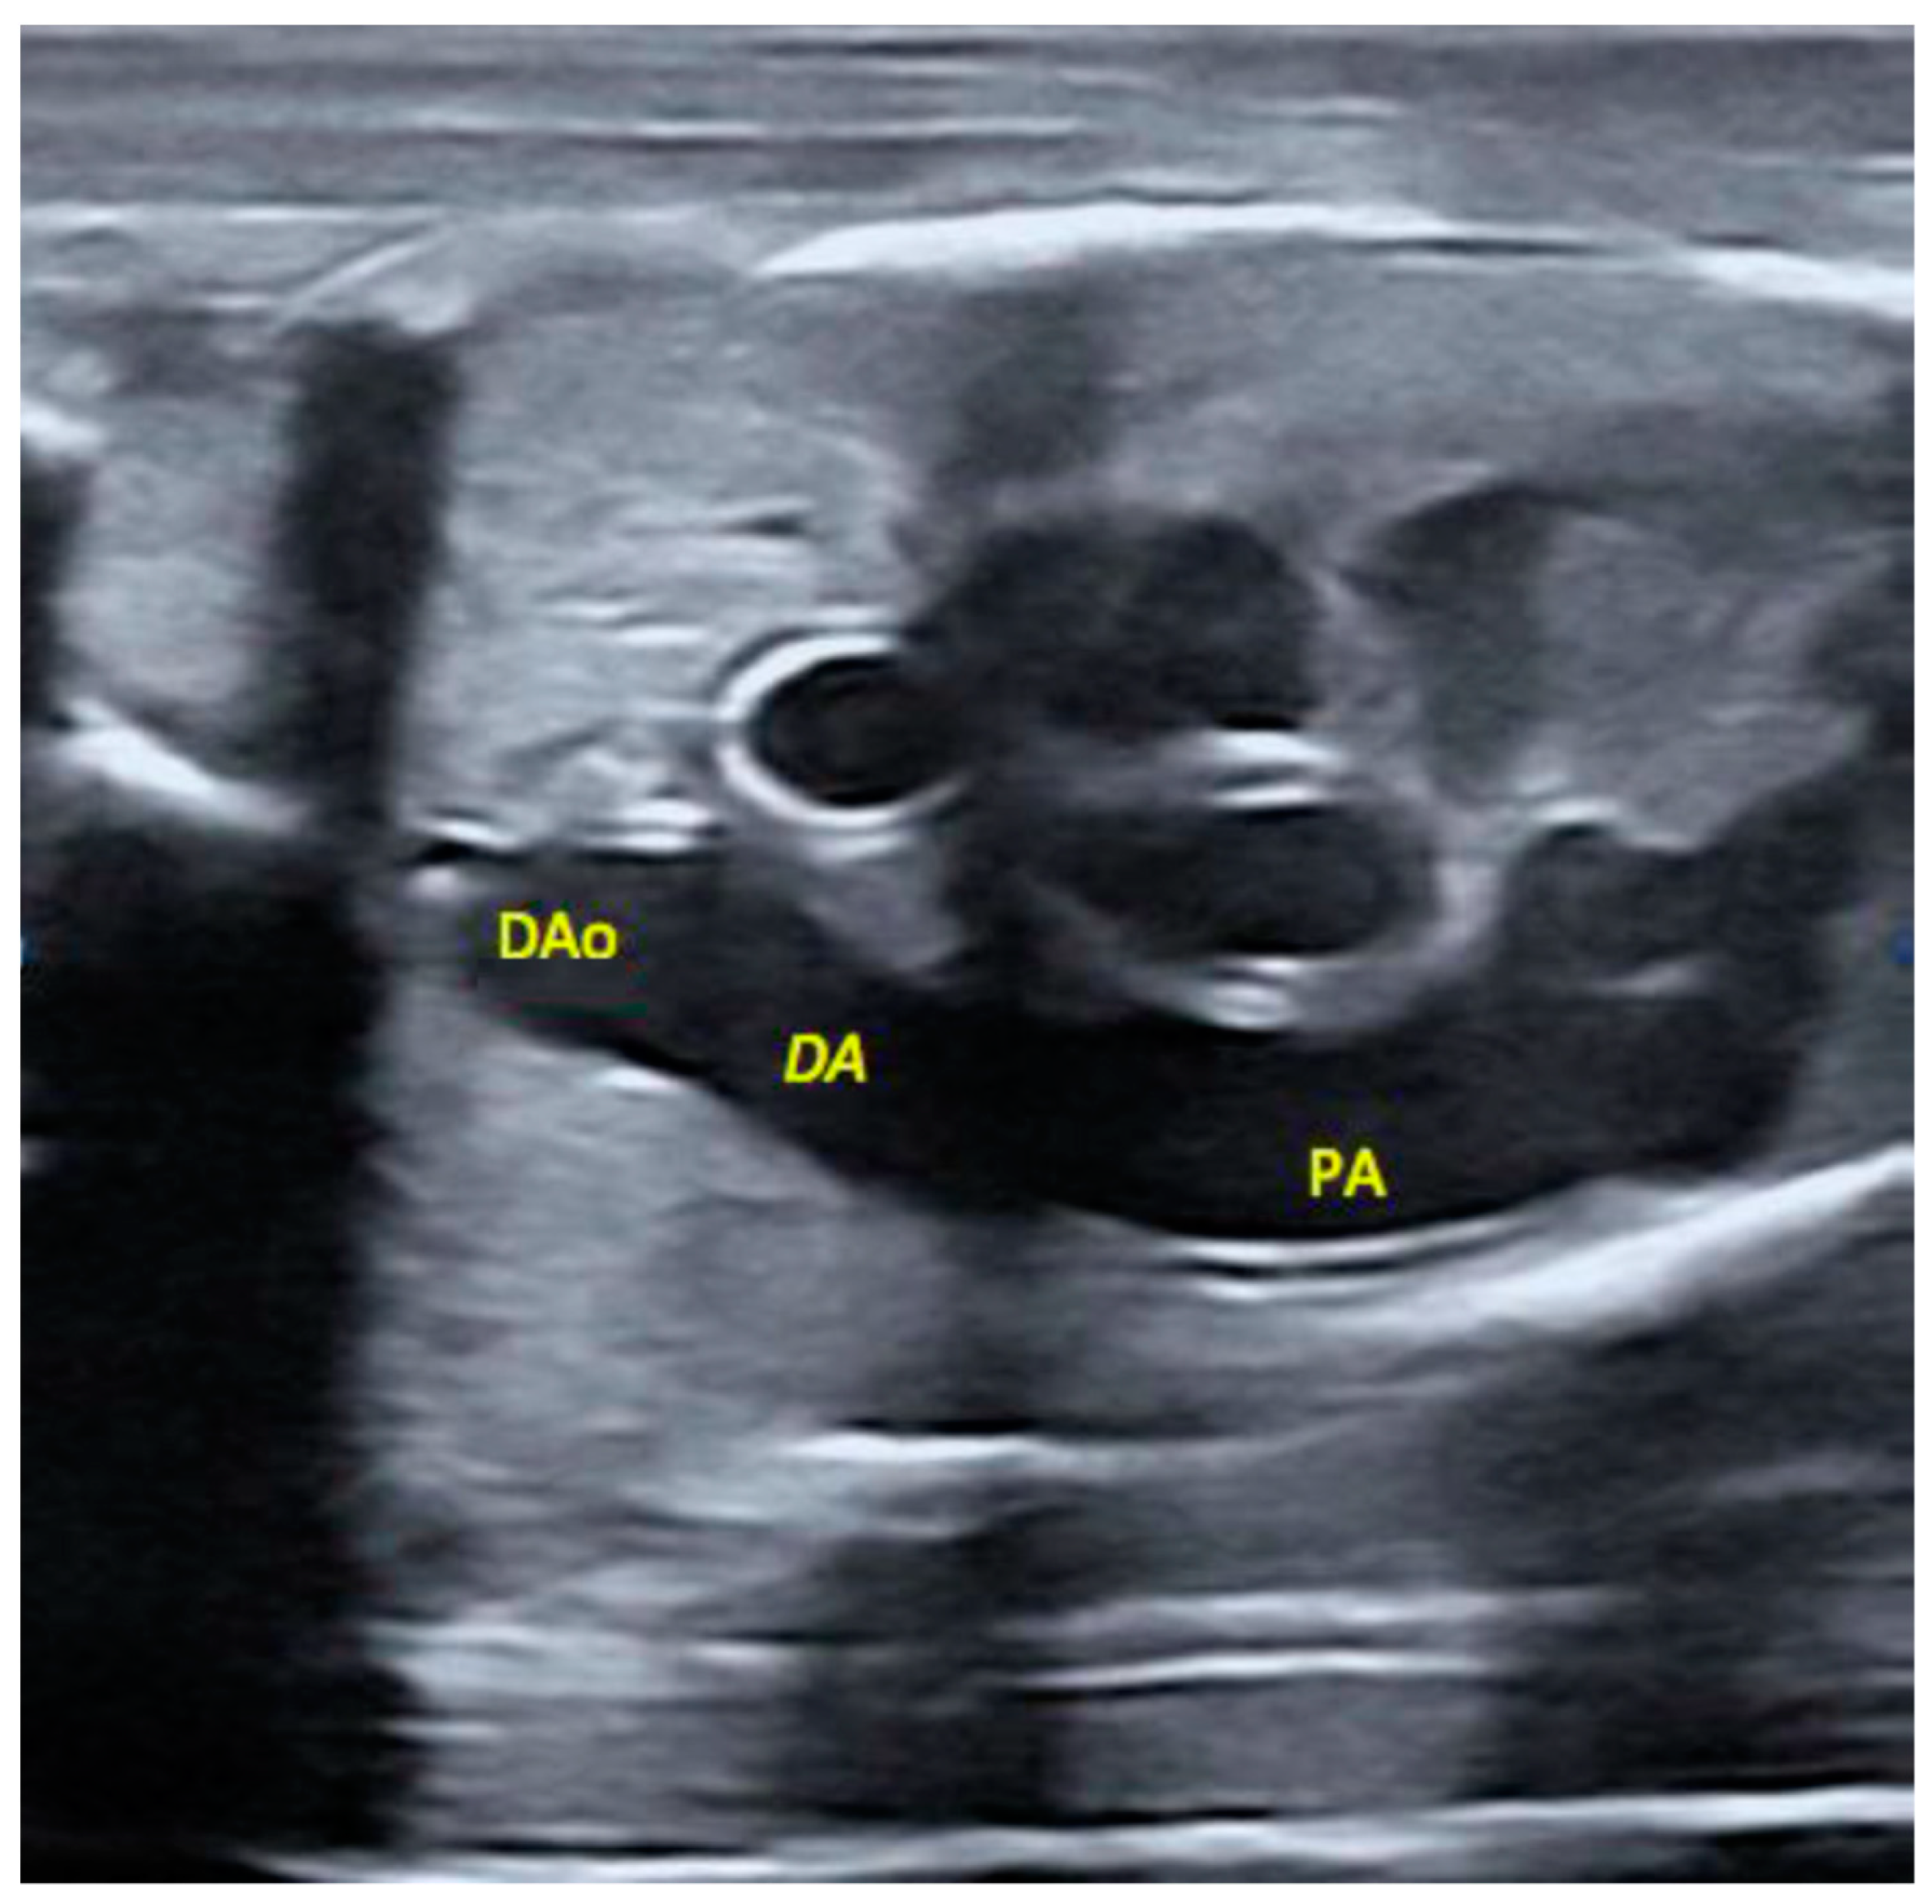

2.5. Morphological Appearance of Fetal Descending Aorta and Ductus Arteriosus